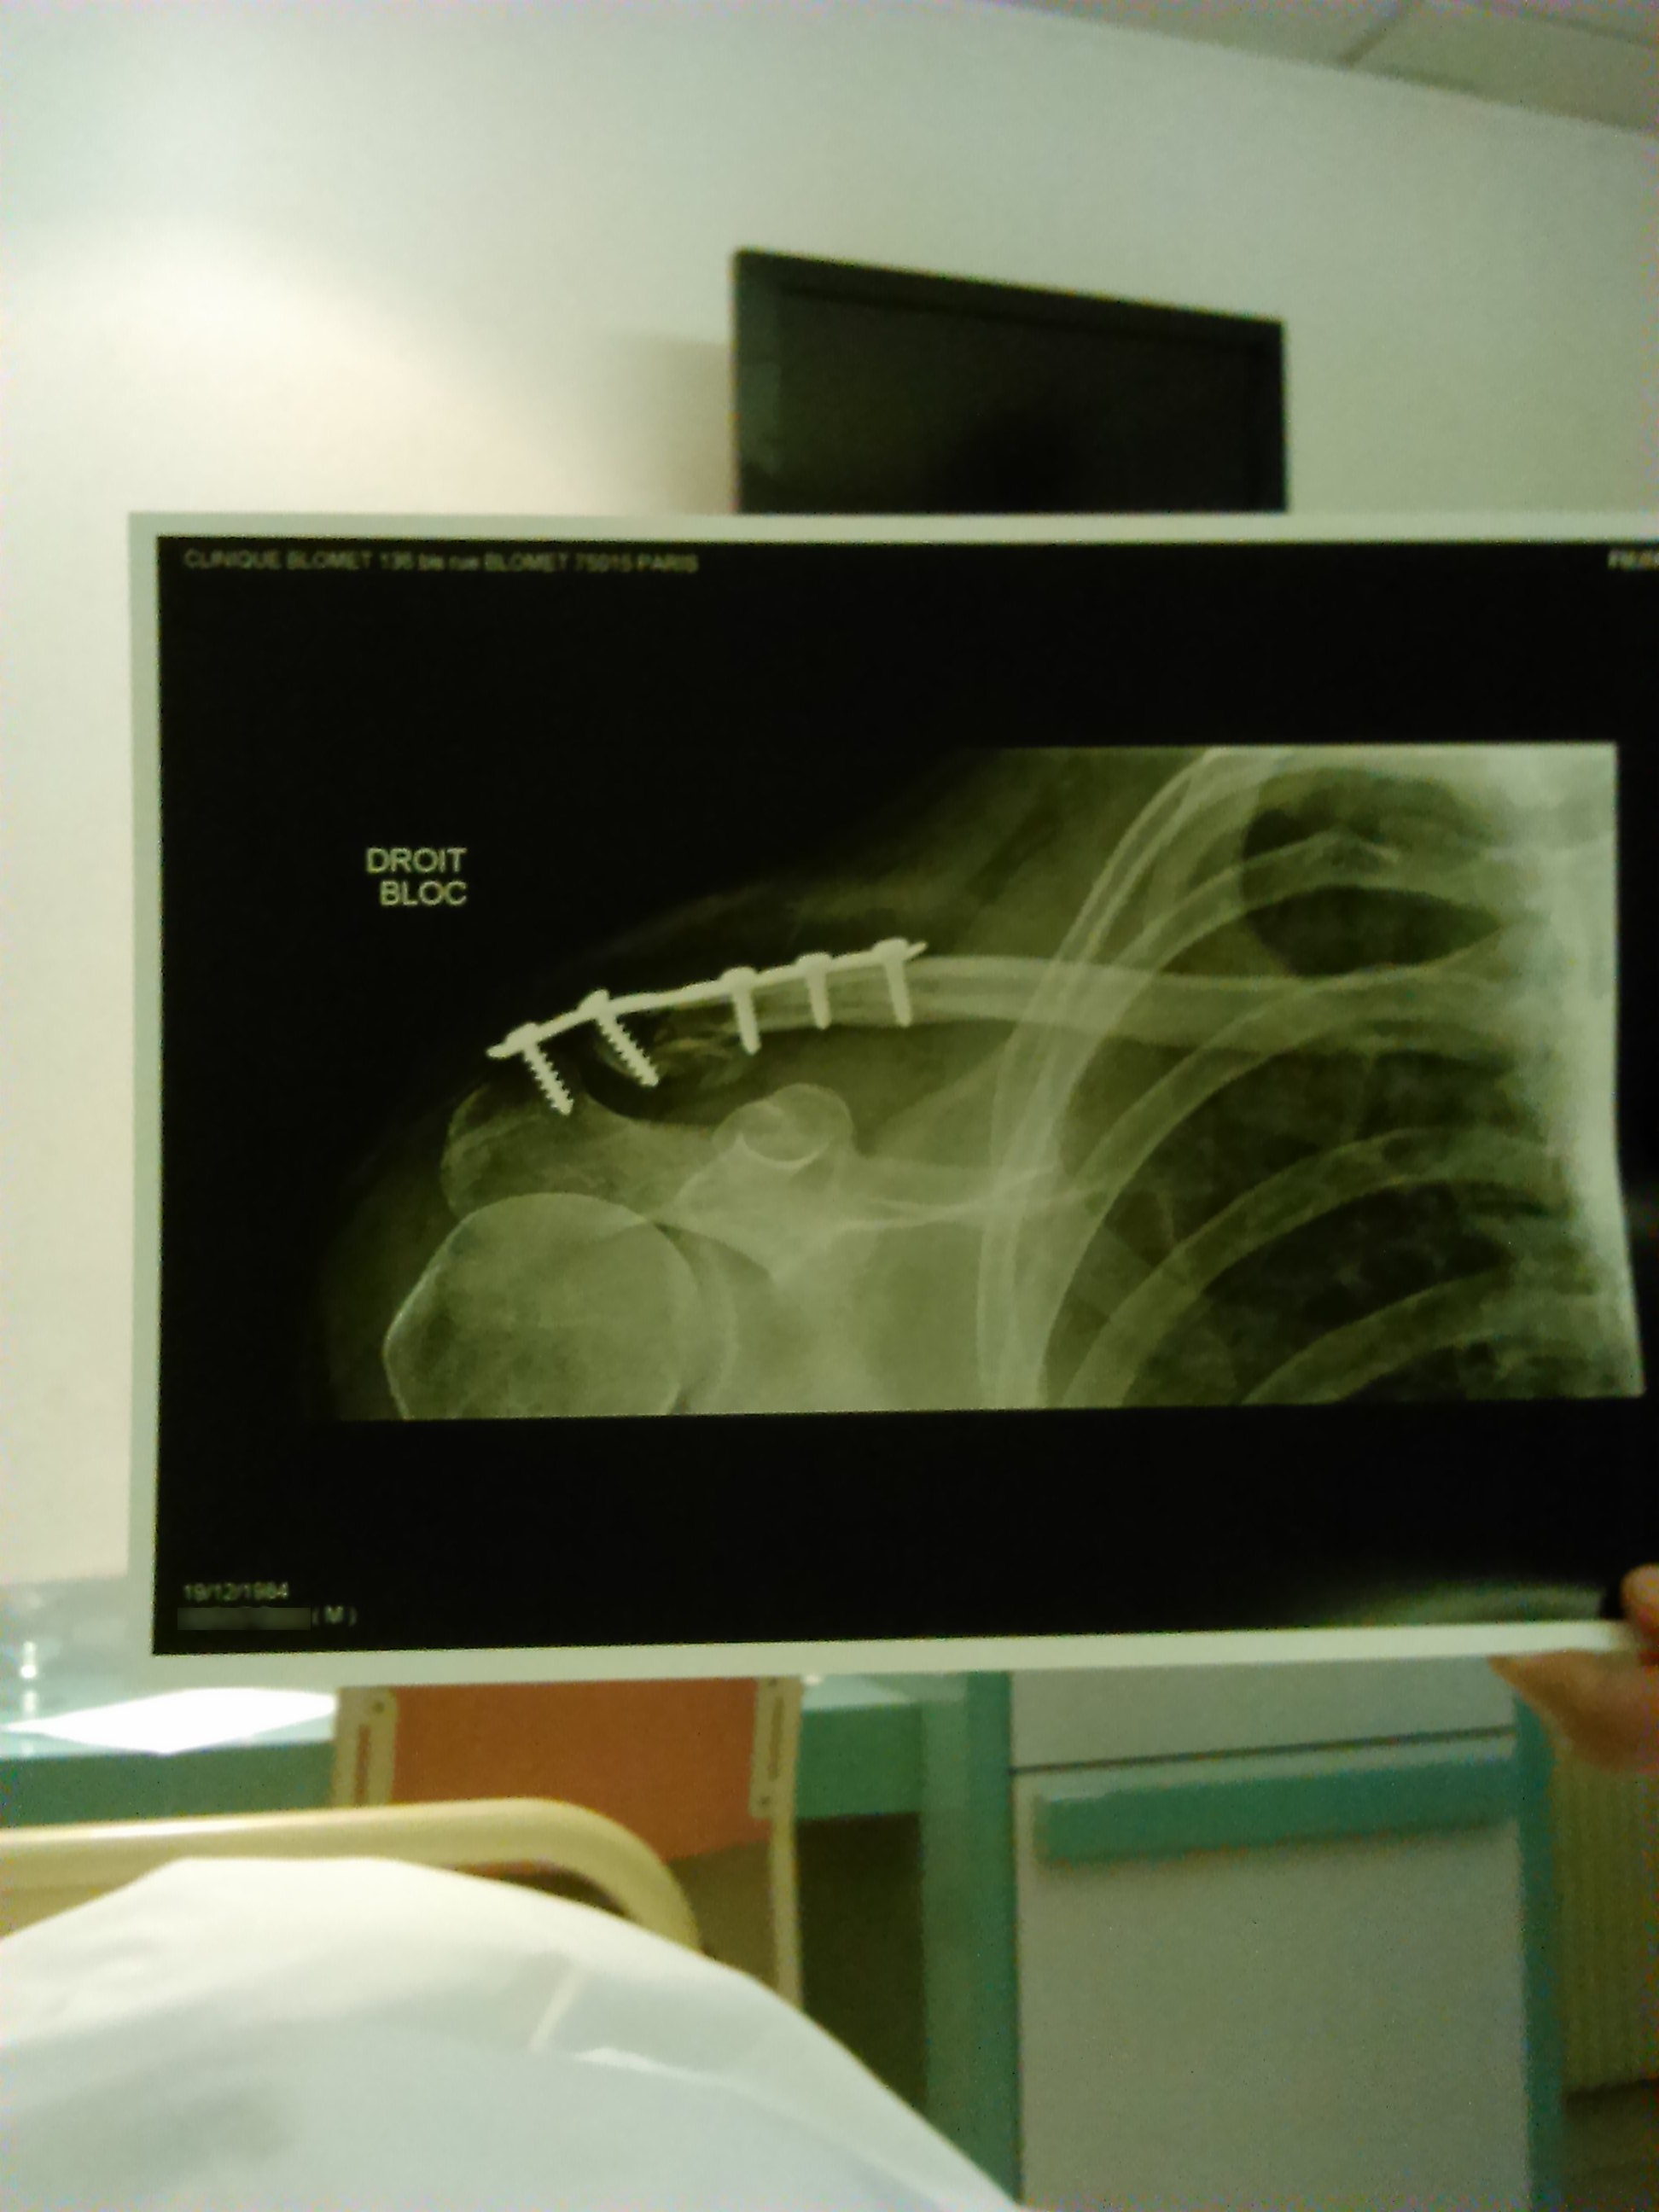

Zeph Le 11/02/2015 à 22:52 Normalement oui, à ma connaissance ça rentre dans ce cas, du coup j'ai fait figurer les skis dans la liste des frais que j'aimerais me faire rembourser (ça, mon masque qui s'est cassé aussi, le reste c'est que des soins et secours). J'attends la réponse de l'assurance pour voir si c'est recevable.